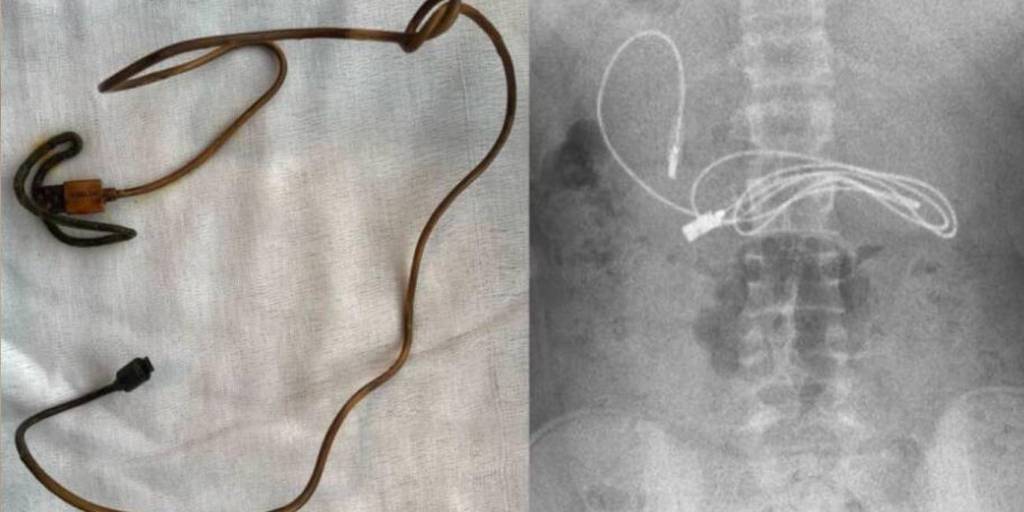

Los profesionales realizaron una serie de exámenes y se percataron de la presencia del cable y además una liga elástica para cabello en su interior. El joven tuvo que ser intervenido quirúrgicamente de emergencia.

Tuvimos dificultades para quitar el cable, ya que un extremo había pasado al intestino delgado”, dijo Yasar Dogan, gastroenterólogo que recurrió a una endoscopía a través de la boca para extraer los objetos.